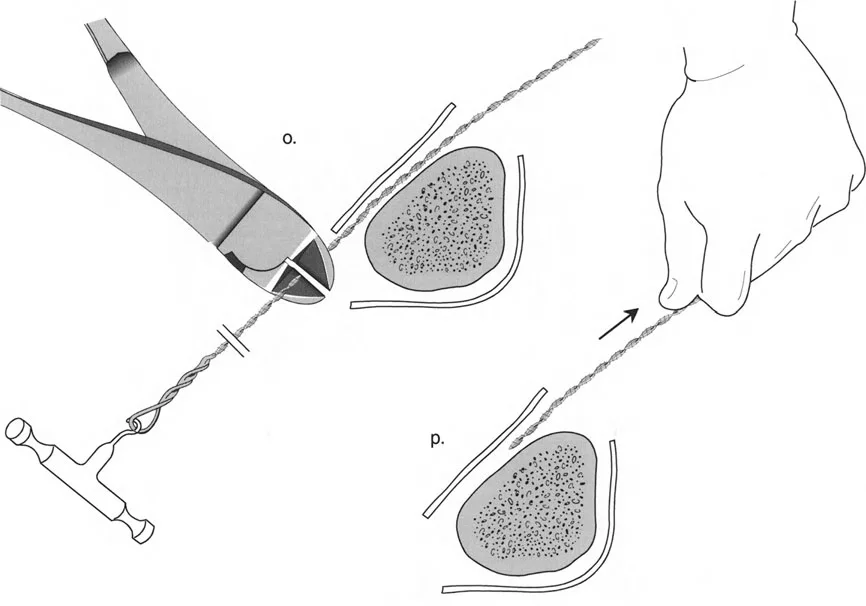

قيود الأسلاك والدبابيس في القاعدة 2

لتحقيق هذه الترجمة الضرورية والمقصودة بسلاسة باستخدام إطار دائري كامل الأسلاك، يلزم استخدام أسلاك الزيتون المعاكسة (counter-opposed olive wires). تعمل أسلاك الزيتون كقوى سحب ديناميكية، تسحب قطعة العظم على طول الحلقة أثناء فتح المفصلات. بدون أسلاك الزيتون، سيبقى العظم ثابتًا بينما تتحرك الحلقة عبر الأنسجة الرخوة، مما يسبب نخرًا شديدًا في الجلد.

على العكس من ذلك، إذا تم استخدام دبابيس نصفية (مسامير شانز)، فإنها تقيد العظم بطبيعتها بالحلقة. نظرًا لأن الدبابيس النصفية هي أذرع صلبة (مثبتة من طرف واحد بالحلقة ومغروسة في العظم من الطرف الآخر)، فإنها لا تسمح للعظم بالانزلاق على طول محور السلك. هذا يجعل أسلاك الزيتون غير ضرورية للترجمة في منشآت الدبابيس النصفية، ولكنه يتطلب من الجراح التأكد من أن الدبابيس النصفية قوية بما يكفي (عادةً دبابيس بقطر 5 مم أو 6 مم مطلية بهيدروكسي أباتيت) لتحمل لحظات الانحناء الناتجة عن الترجمة.

| تقابل الأسلاك | استخدم ما لا يقل عن سلكين زيتون متقابلين لكل قطعة إذا كنت تتجنب الدبابيس النصفية. | الأسلاك الزيتون الفردية ستسبب قصًا ودورانًا غير مرغوب فيه حول محور السلك. |